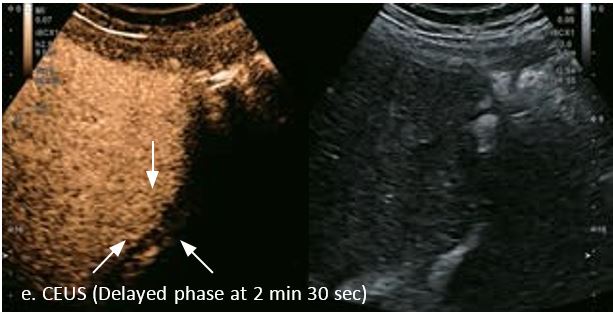

LI-RADS 4 множинні ГЦК

Це випадок 60-річної жінки з декомпенсованим цирозом печінки з асцитом. На сірошкальному зображенні можна виявити два вогнищевих ураження, розміром 21 мм і 10 мм відповідно, розташовані в сегменті 5. Оскільки дослідження методом зсувної хвилі на апараті Canon виконується штовхаючим імпульсом, пацієнтам з асцитом не можна проводити дослідження за допомогою зсувної хвилі, для визначення стадії фіброзу. На ранній артеріальній стадії гомогенне гіперехогенне підсилення спостерігається в обох ураженнях. Ураження є ізоехогенними в портальній венозній та пізній фазах, вимивання не спостерігається через 6 хвилин після ін'єкції, тому ці ураження були класифіковані як LI-RADS 4, ймовірна ГЦК. Важливо знати, що LI-RADS 5 - це ГЦК зі 100% вірогідністю, і вона не потребує біопсії. Значна кількість LI-RADS M (ймовірно або точно злоякісні, але не специфічні для ГЦК) і LI-RADS 4 (ймовірна ГЦК) насправді являються ГЦК.

Малюнок 11